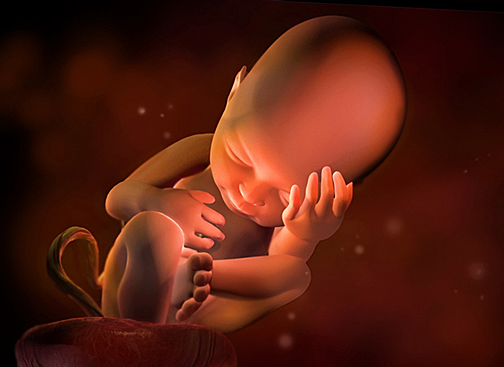

Desarrollo embrionario

Periodo que se produce entre la fecundación y el parto, dura normalmente 9 meses